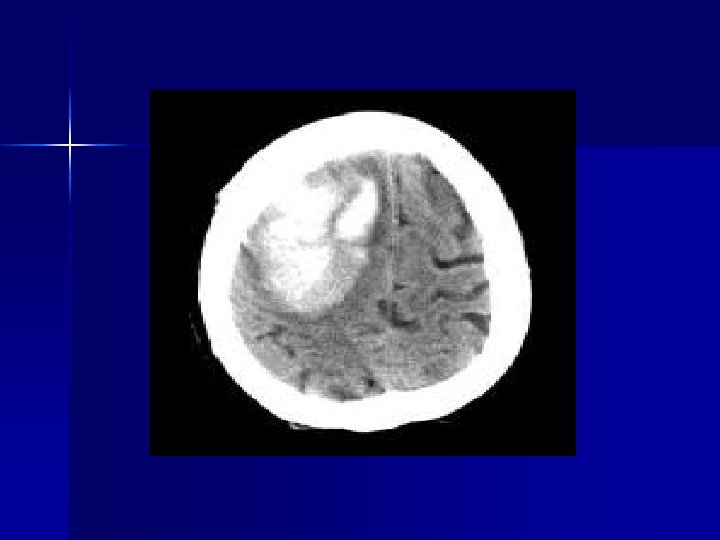

Intraparenchymal Hemorrhage n n 55% report headache at onset of symptoms Suspicion if hypertension, known mass, bleeding diathesis, trauma Support ABCs REMO protocol Hypertensive Emergency if SBP>220, DBP>120 – EKG, IV, O 2, monitor – NTG, metoprolol for chest pain, pulm edema